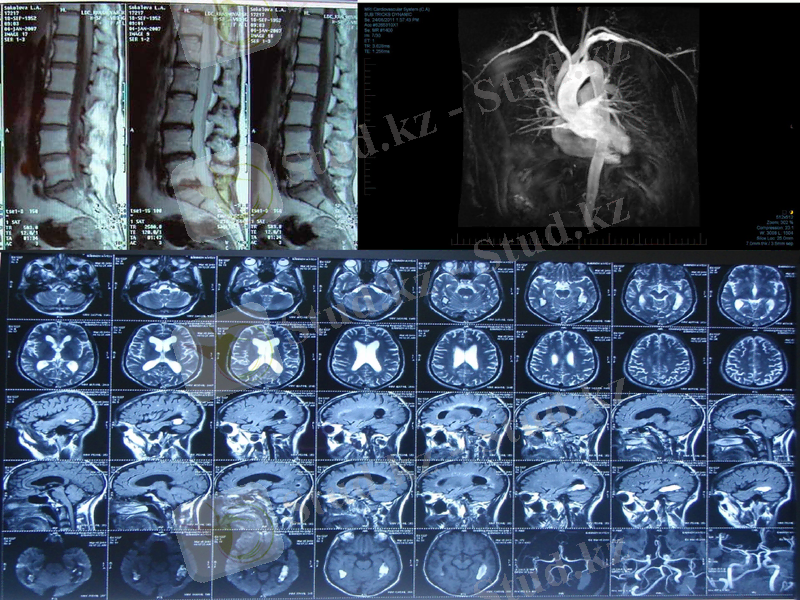

Магнитттік-резонансты томография

Магнитті-резонанстық томография (МРТ) - бұл ядролық магниттік резонанс негізінде құрылған бейнелеу әдістерінің бірі. МРТ бас және жұлын, жүрек қантамырларын, сүйек бұлшық ет жүйелерін зерттеуде қолданады. КТ әдісінен артықшылығы біріншіден науқасқа гамма сәулелері әсер етпейді, екіншіден МРТ-ның бейнелерді жоғарғы айыру қабілеттілігі, бейнелердің жоғарғы контрастілігі және әр түрлі жазықтықтардағы қималарды алу мүмкіндігі. МРТ ісіктің нақты көлемін және оның ағзада таралу аймағын анықтай алады.